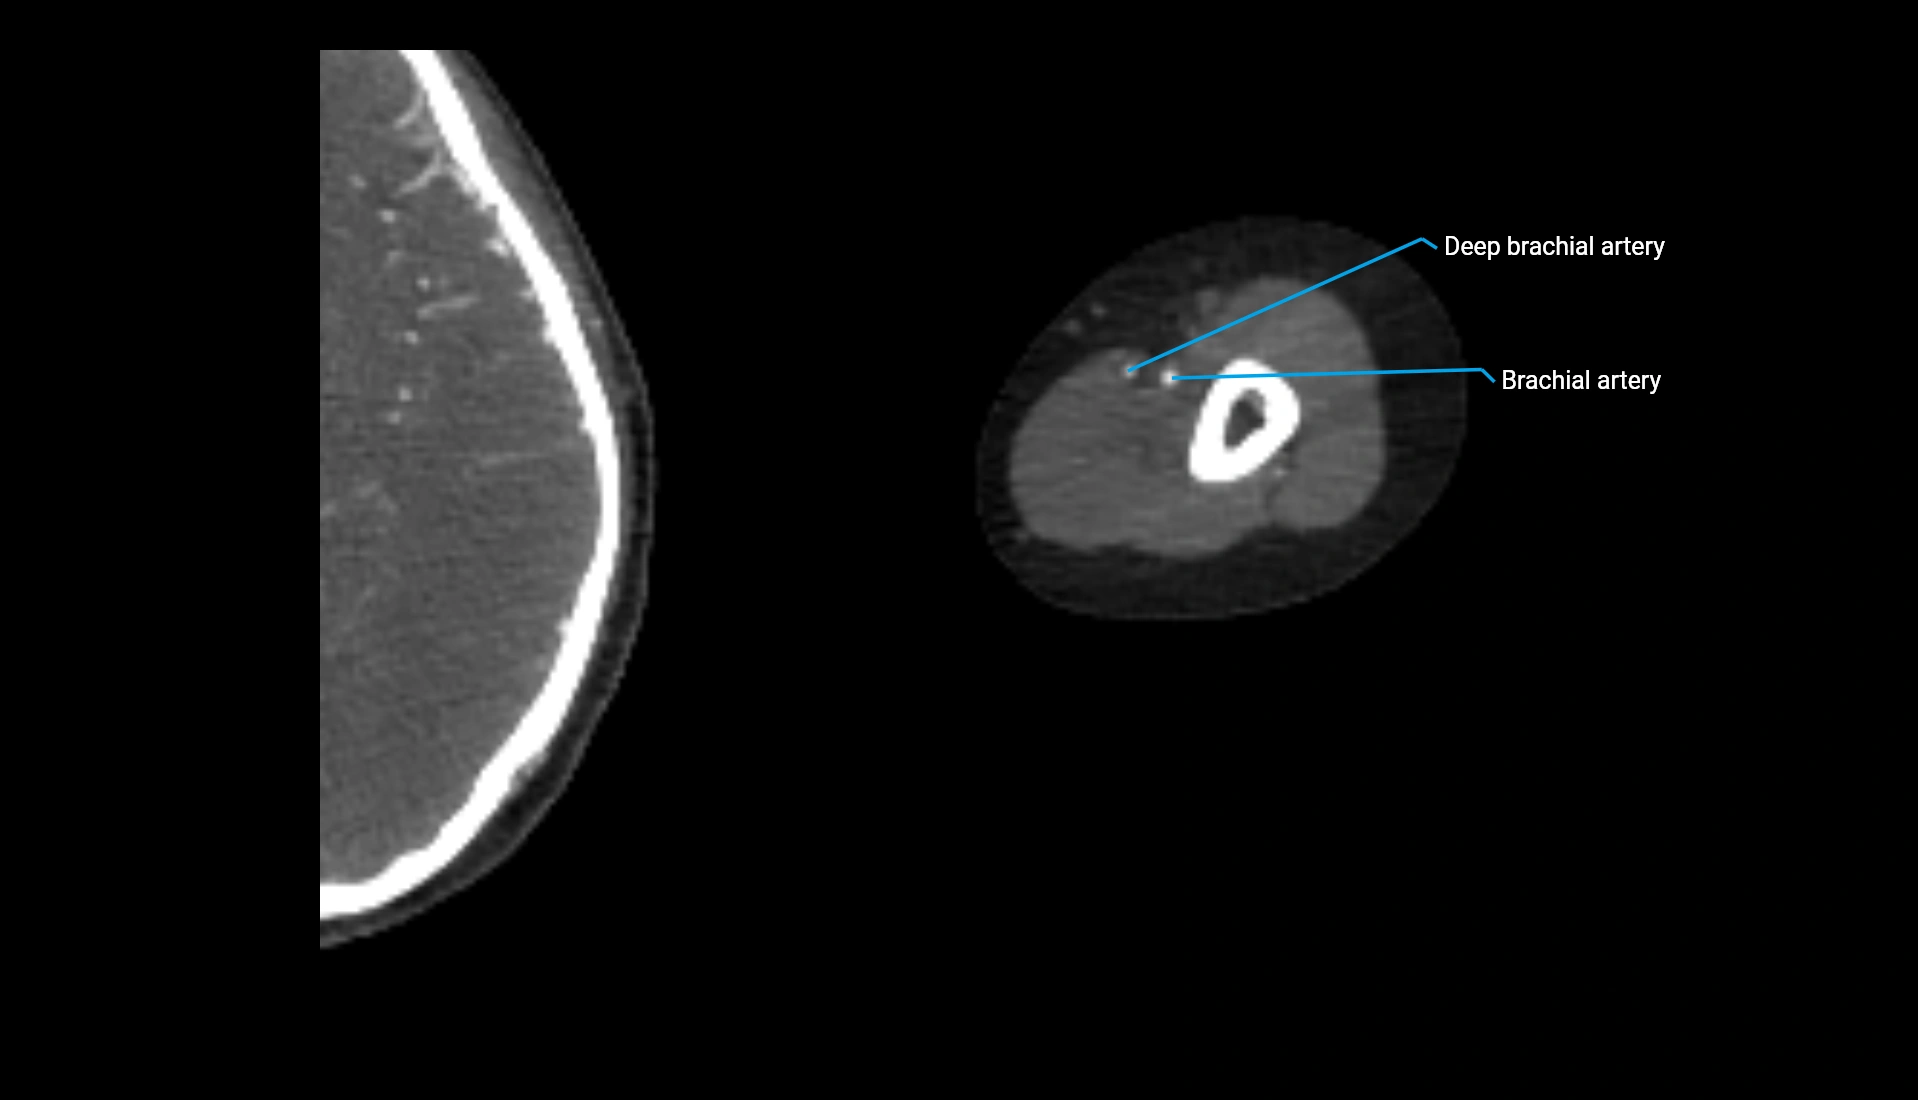

CT Appearance

Non-Contrast CT:

• Cortex: High-density, sharply defined

• Subchondral bone: Dense cancellous matrix

• Articular surface: Smooth concave contour articulating with the capitellum

• Excellent for evaluating bone integrity, alignment, and subtle fractures